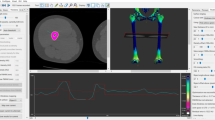

CT Data acquisition and reconstruction planes

All measurements were carried out on the the aycan® workstation OsiriX (aycan Medical Systems®, Rochester, NY, USA). A detailed list of the performed measurements is to be found in Table 1.

Measurements

The first author (AD) performed all measurements twice at a minimum interval of two months. The final values presented in the current study and all further analysis was based on the mean values of these two readings. The same measurements were performed by the senior author (AJ) independently. Both observers were blinded to each other’s results. Both observers performed the measurement according to a well-defined plane configuration set a priori (Table 1). The two readings of the first observer were compared to assess the intrarater reliability. The readings of the first and the second observer were compared to evaluate the interrater reliability.